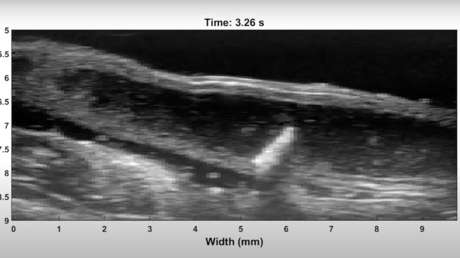

En teoría estos pequeños dispositivos pueden ser utilizados para introducirse en distintas vísceras humanas, pero los primeros experimentos tuvieron como polígono de pruebas el colon de un ratón, donde el microrrobot se mostró capaz de moverse en la dirección opuesta a los fluidos naturales. El dispositivo fue introducido en el roedor a través de la anestesia en una solución salina y luego los científicos recurrieron al ultrasonido para observar en tiempo real los desplazamientos del pequeño aparato.